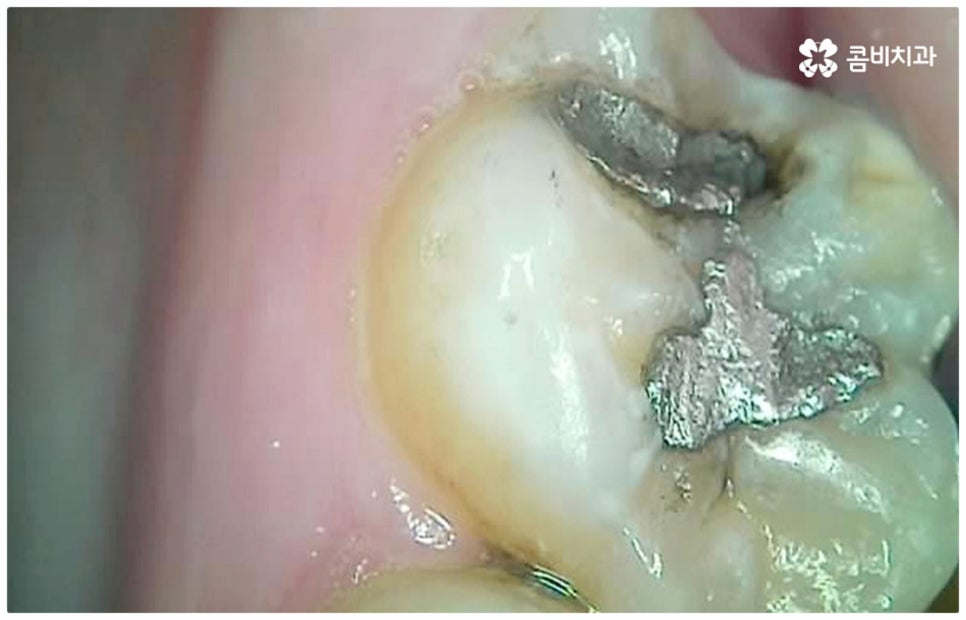

모든 치아가 각자의 역할을 가지고 있지만 특히 어금니의 경우 가장 크고 단단하여 저작 기능의 핵심 역할을 맡고 있는 만큼 굉장히 중요한 치아라고 할 수 있습니다. 그런데 구강 가장 안쪽에 있기 때문에 관리하기가 까다롭고 평상시에도 음식물 찌꺼기가 남아있기 쉬워 주변 잇몸이 부어오르면서 염증이 생기거나 충치가 생길 가능성이 높은 치아라서 관리하실 때 특별히 주의하실 필요가 있어요. 충치가 한 번 발생하여 치아 안쪽으로 감염이 진행되면 통증이 점점 심해져서 나중에는 일상 생활이 어려워질 정도가 될 수도 있고 결국 치아뿌리염증으로 번져 발치를 해야하는 상황에 이를 수도 있기 때문에 발견 즉시 어금니충치치료 를 받아주시는 게 좋을 거예요.

만약 충치가 어느 정도 진행되어 상아질까지 손상되면 비로소 시리거나 쑤시는 듯한 통증이 생기며 이 때 치과에 내원하시면 정도에 따라 감염 부위를 제거하고 어금니충치치료 방법 중 인레이 또는 온레이를 통해 수복하게 되는데, 이 시기를 지나 병증이 더욱 심해지면 내부 치수조직을 제거하는 신경치료를 진행하게 될 거예요.